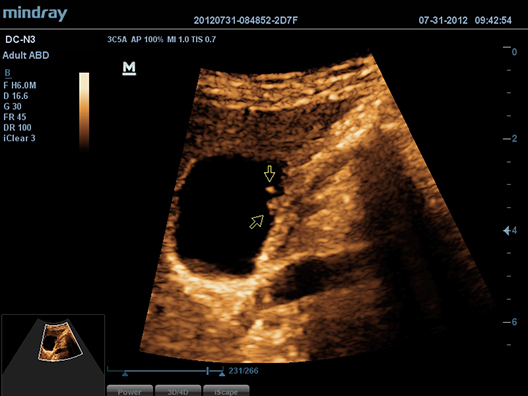

–ò–∑–æ–ª–∏—Ä–æ–≤–∞–Ω–Ω–∞—è –≥–∞—Ä–º–æ–Ω–∏—á–µ—Å–∫–∞—è –≤–∏–∑—É–∞–ª–∏–∑–∞—Ü–∏—è –¥–ª—è —É–ª—É—á—à–µ–Ω–∏—è –∫–æ–Ω—Ç—Ä–∞—Å—Ç–Ω–æ–≥–æ —Ä–∞–∑—Ä–µ—à–µ–Ω–∏—è, –æ–±–µ—Å–ø–µ—á–∏–≤–∞—é—â–∞—è –±–æ–ª–µ–µ —á–µ—Ç–∫–æ–µ –∏–∑–æ–±—Ä–∞–∂–µ–Ω–∏–µ —Å –ø—Ä–µ–≤–æ—Å—Ö–æ–¥–Ω—ã–º –ø—Ä–æ—Å—Ç—Ä–∞–Ω—Å—Ç–≤–µ–Ω–Ω—ã–º —Ä–∞–∑—Ä–µ—à–µ–Ω–∏–µ–º –∏ –º–µ–Ω—å—à–∏–º —É—Ä–æ–≤–Ω–µ–º —à—É–º–∞.

iClearTM

–ü–æ–∑–≤–æ–ª—è–µ—Ç —É–ª—É—á—à–∏—Ç—å –∫–∞—á–µ—Å—Ç–≤–æ –∏–∑–æ–±—Ä–∞–∂–µ–Ω–∏—è, –æ—Å–Ω–æ–≤—ã–≤–∞—è—Å—å –Ω–∞ –∞–≤—Ç–æ–º–∞—Ç–∏—á–µ—Å–∫–æ–º —Ä–∞—Å–ø–æ–∑–Ω–∞–≤–∞–Ω–∏–∏ —Å—Ç—Ä—É–∫—Ç—É—Ä.

- –ë–æ–ª–µ–µ —á–µ—Ç–∫–∏–µ –∫—Ä–∞—è –∏ –∫–æ–Ω—Ç—É—Ä—ã

- –ü–ª–∞–≤–Ω–æ–µ –∏ –æ–¥–Ω–æ—Ä–æ–¥–Ω–æ–µ –æ—Ç–æ–±—Ä–∞–∂–µ–Ω–∏–µ —Ç–∫–∞–Ω–µ–π

- –°–Ω–∏–∂–µ–Ω–∏–µ –∑–µ—Ä–Ω–∏—Å—Ç–æ—Å—Ç–∏ –≤ ?–æ–±–ª–∞—Å—Ç—è—Ö –±–µ–∑ —ç—Ö–æ—Å–∏–≥–Ω–∞–ª–∞?